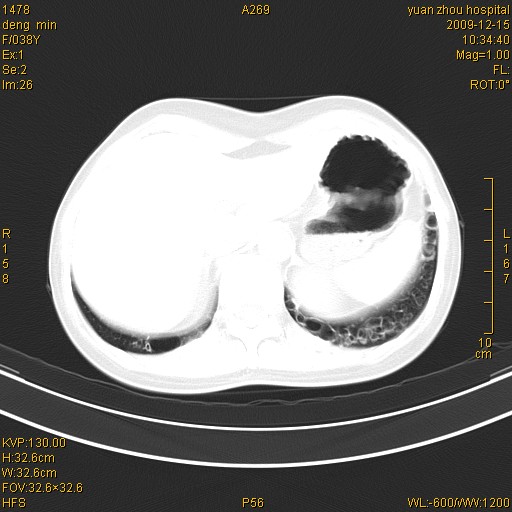

标题: CT23919:F38Y 咳嗽月余 [打印本页]

标题: CT23919:F38Y 咳嗽月余

支扩并感染

支扩感染

右肺中下叶、左肺上叶舌段及左肺下叶支气管扩张合并感染。